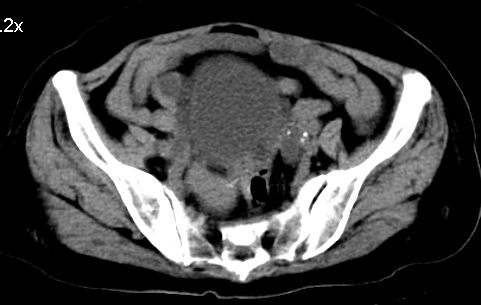

标题: CT10133:F、74岁,反复血尿10天。 [打印本页]

标题: CT10133:F、74岁,反复血尿10天。

膀胱癌突破浆膜可能性大

考虑膀胱癌可能性大伴双侧输尿管下端扩张.

1.膀胱后壁见不规则致密影,占位?膀胱内凝血块?建议俯卧位扫描、膀胱镜检查.

2.双侧输尿管下段扩张.

膀胱三角区不规整软组织改变,双侧输尿管扩张,所以占位性病变肯定首先考虑,建议改变体位扫描除外游离血块影,但老年人出血原因一定要查明。

1.膀胱后壁见不规则致密影,随体位改变,为膀胱内凝血块;

2.双侧输尿管下段扩张.输屎管结石可能大。建议作进一步检查。